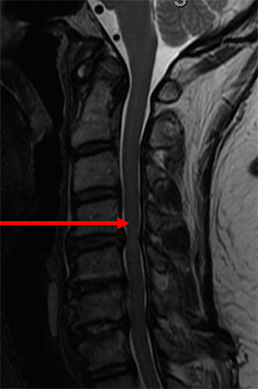

Clinical Example

48 year old cook presents with dropping her kitchen tools and feeling clumsy. MRI shows severe spinal cord compression. The spinal cord is bruised as well (arrow). The left image is a side view. The middle view is a cross section of a normal spine. The right shows the spinal cord (arrow) being compressed.

Because of her age and wanting flexibility, we did a laminoplasty. We created more room for her spine and did not do a fusion. It is motion preserving. Left image is a side view MRI showing more space for the spinal cord. The middle picture is a cross section of the same level that showed cord compression now wide open.